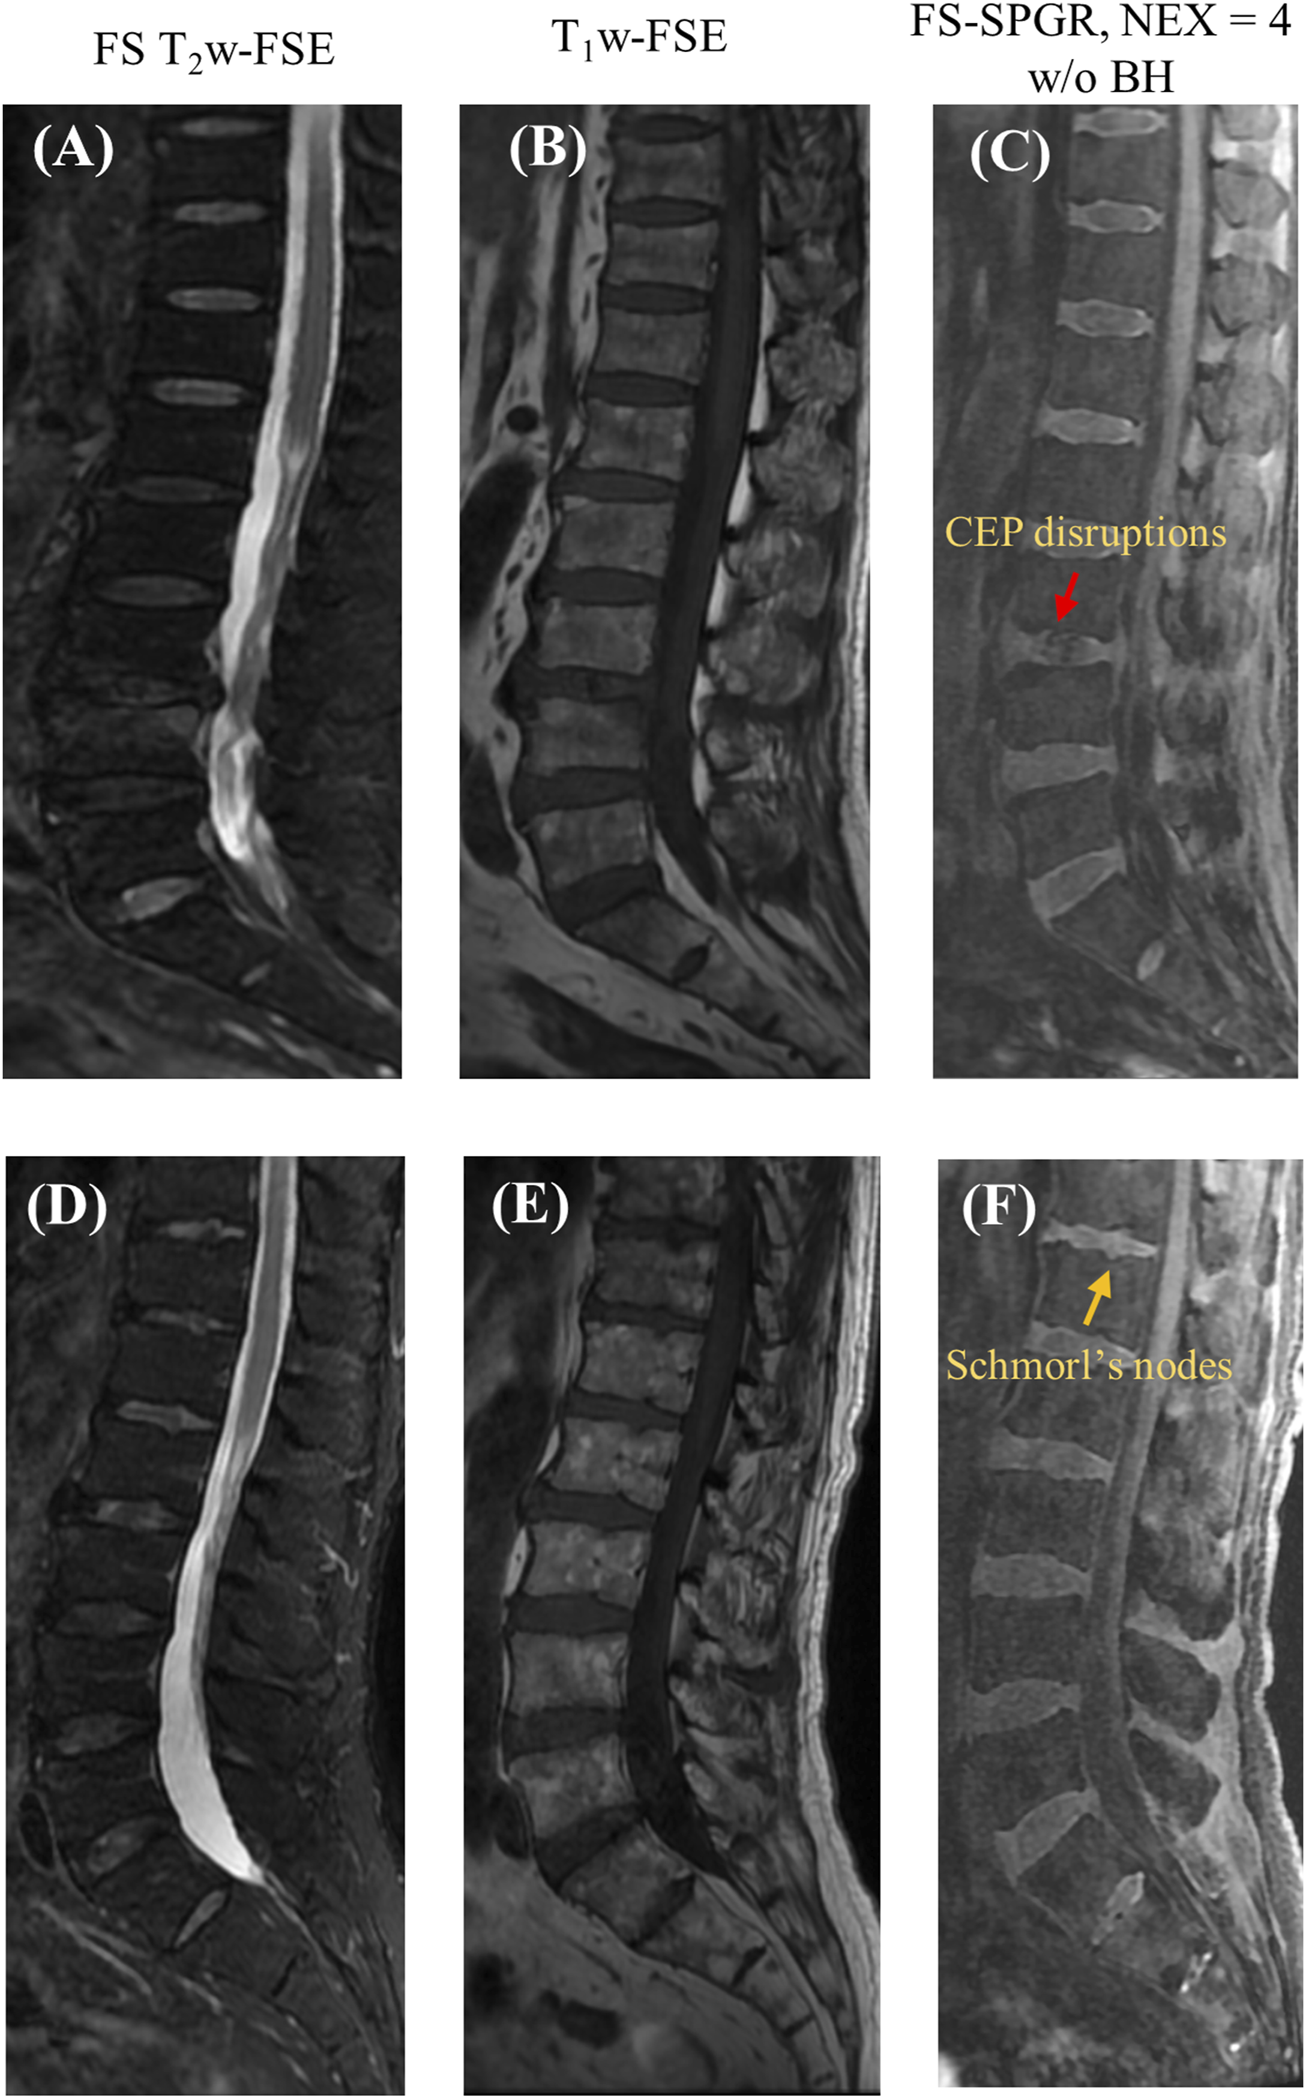

Figure 5 presents two rows of the FS-SPGR images alongside the routine clinical sequences for another two male subjects (63 and 67 years old, respectively) with lower back pain. The first row shows a longer segment of CEP disruption at this level of degenerative disc disease, while the second row shows visibly delineated Schmorl’s nodes.

FIGURE 5

Clinical FS T2w-FSE (A,D) and T1w-FSE (B,E) images as well as 3D FS-SPGR (free breathing, NEX = 4) (C,F) images acquired from two patients with lower back pain (first row: 63-year-old male; second row: 67-year-old male). The CEP disruptions are pointed by red arrow and Schmorl’s nodes are indicated by yellow arrows in panels (C,F), respectively.